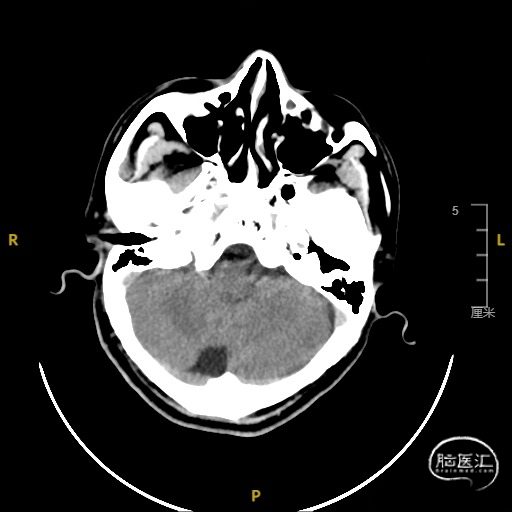

➢ 脑血管造影检查

患者主因言语不利3天入院,头核磁提示右侧额、顶叶多发低灌注梗塞,脑血管造影提示右侧颈内动脉开口重度狭窄,为责任血管,另外患者前交通动脉、右侧后交通动脉开放不良,并且狭窄严重,考虑到高灌注风险,决定分期处理,一期小球囊扩张改善供血,二期支架成型。